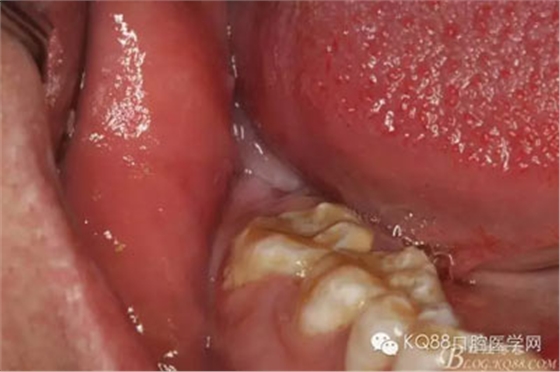

1.術(shù)前的患者口內(nèi)像:48未萌出,無(wú)盲袋、頰側(cè)輕度膨隆